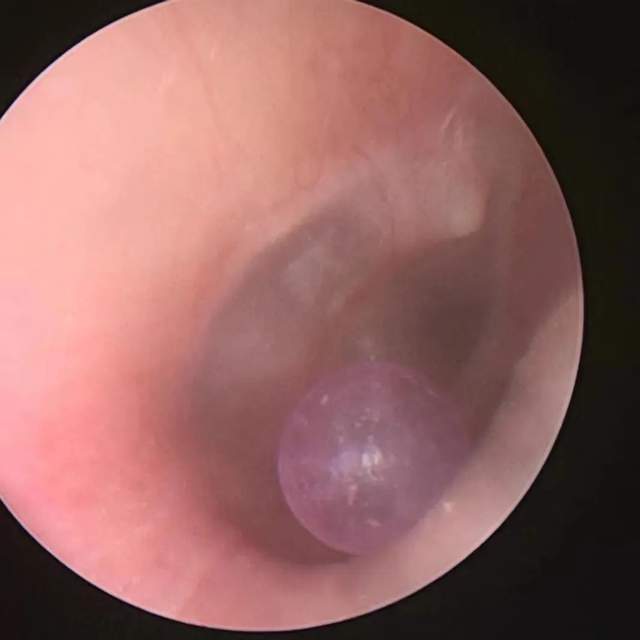

耳朵进了东西怎么办?_异物

图片尺寸572x526